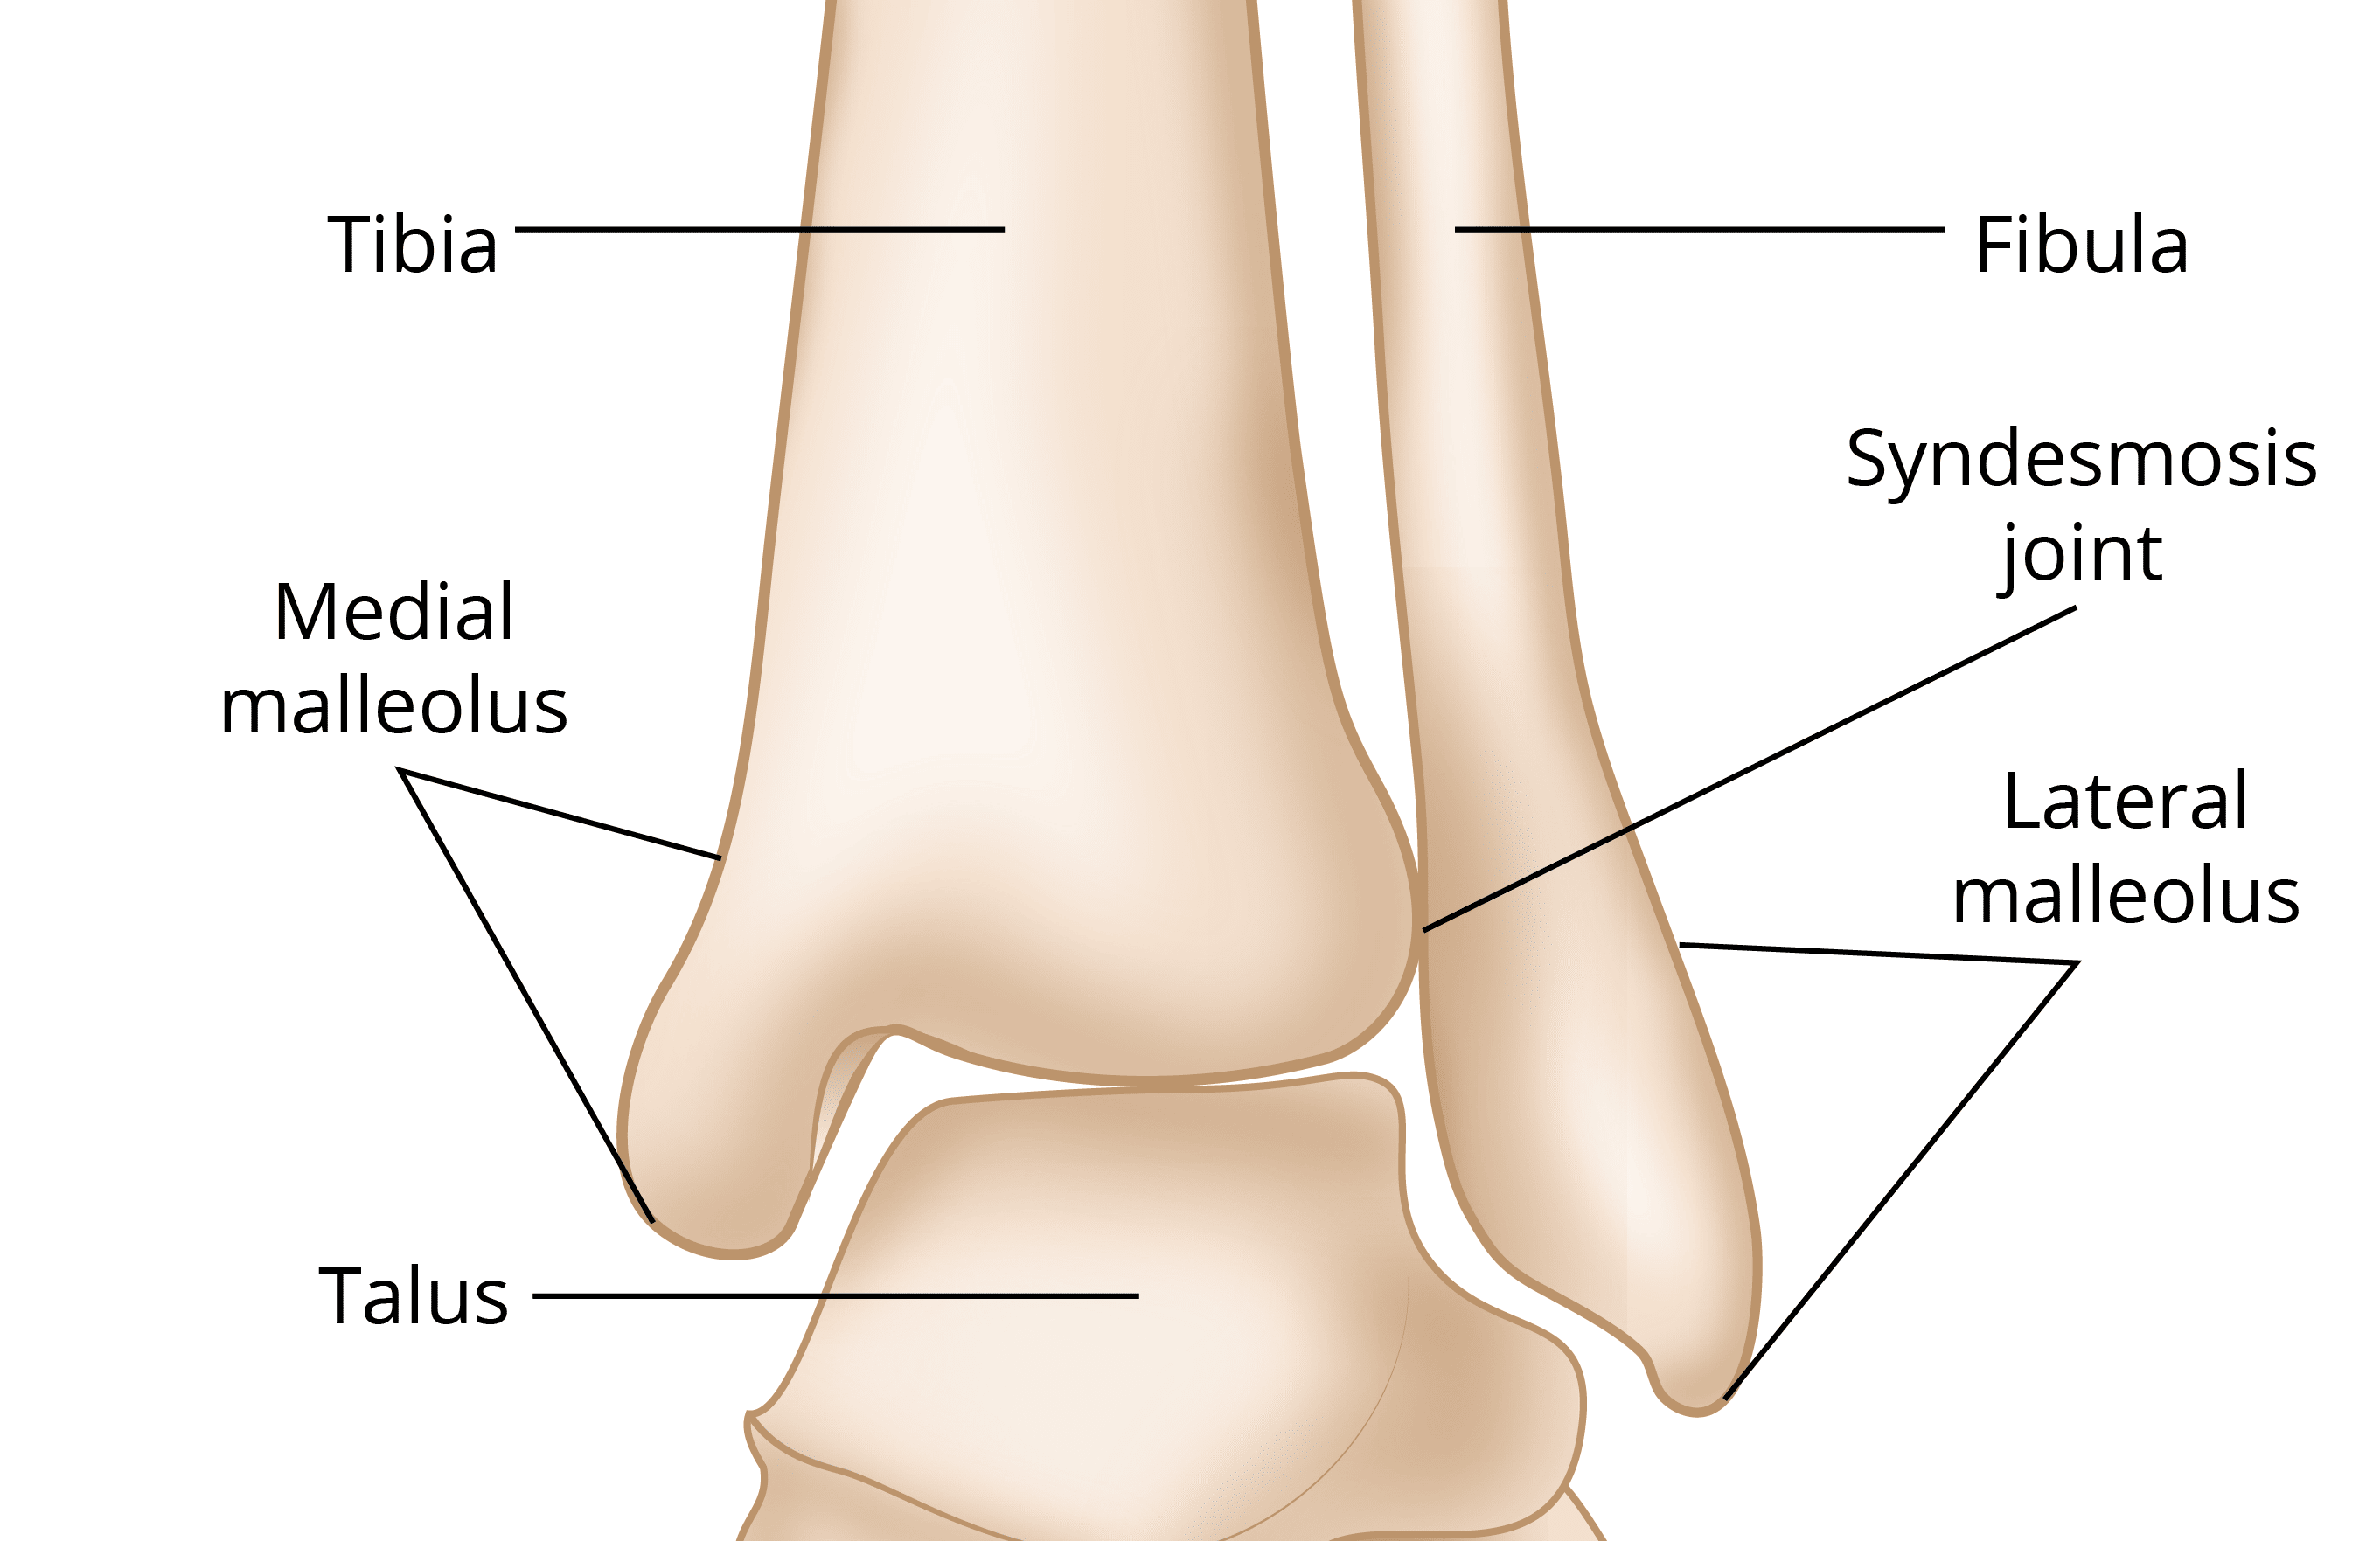

what are the joints of the ankle complex?

distal tibiofibular joint

talocrural joint

subtalar joint

what type of joint is the tibiofibular joint?

syndesmosis joint

what are the ligaments of the tibiofibular joint?

anterior inferior tibiofibular (AITF)

posterior inferior tibiofibular (PITF)

what is the talocrural joint?

known as the ankle joint

what can the talocrural joint also be classified as?

mortise joint

tibiotalar joint

fibulotalar joint